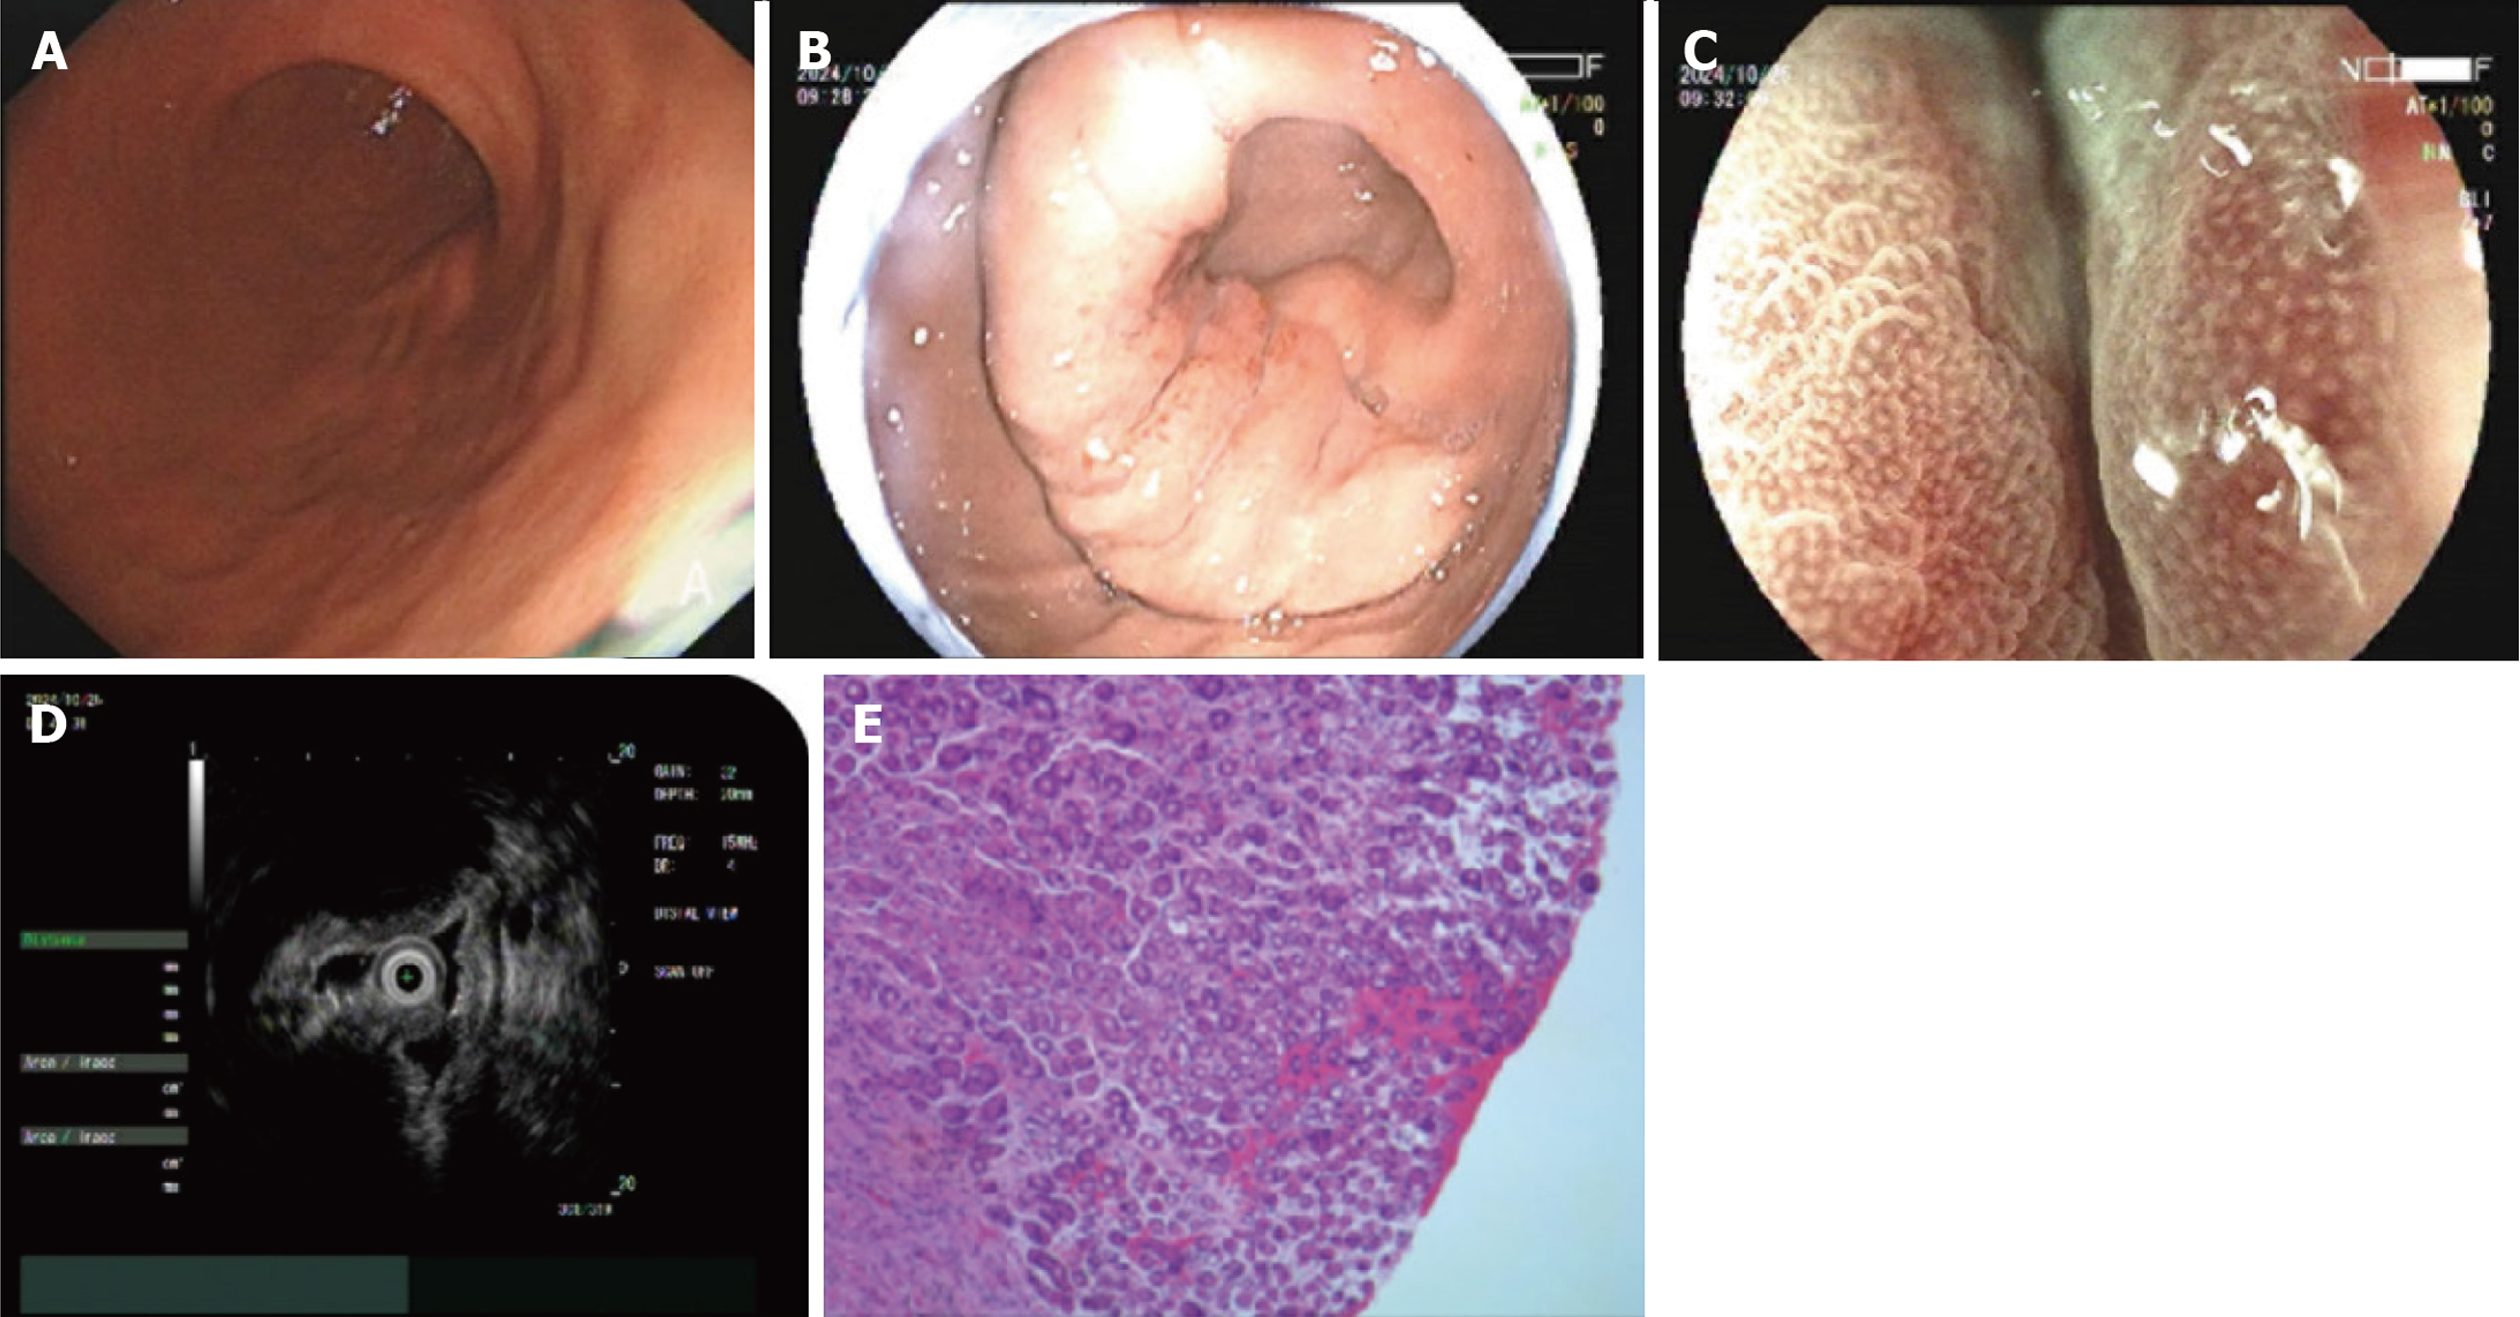

病例2: 激光超声胃镜示胃体下部前壁1.2 cm×0.8 cm Ⅱa型病变, 表面充血、糜烂, 蓝激光成像(blue laser imaging, BLI)放大观察腺管结构稍紊乱, IMVP(-), DL(-); FUJINON SP702 MPS 15MHz超声探查局部胃壁增厚, 第1、2层呈低回声改变, 3-5层结构尚清晰(图2A和B); 活检病理: (胃体下部前壁)低粘附性癌(粘液腺癌)(图2C).

病例4: 激光超声胃镜提示: 胃体下部大弯侧见黏膜下隆起, 表面充血, 局部胃壁僵硬、蠕动消失. BLI放大观察示IMSP(-), IMVP(-), FUJINON SP702 MPS 15 MHz超声探查见第1、2层回声存在, 第3-5层回声消失、呈低回声改变, 大小约2.6 cm×1.5 cm; 深挖活检后病理提示胃差分化粘液癌. 免疫组化: CKpan(+), CK18(+), CEA(部分弱+), Syn(-), CgA(-), CD56(-), Ki-67(高表达), CD68(-), Vimentin(-), GATA-3(-), P63(-)(图4).